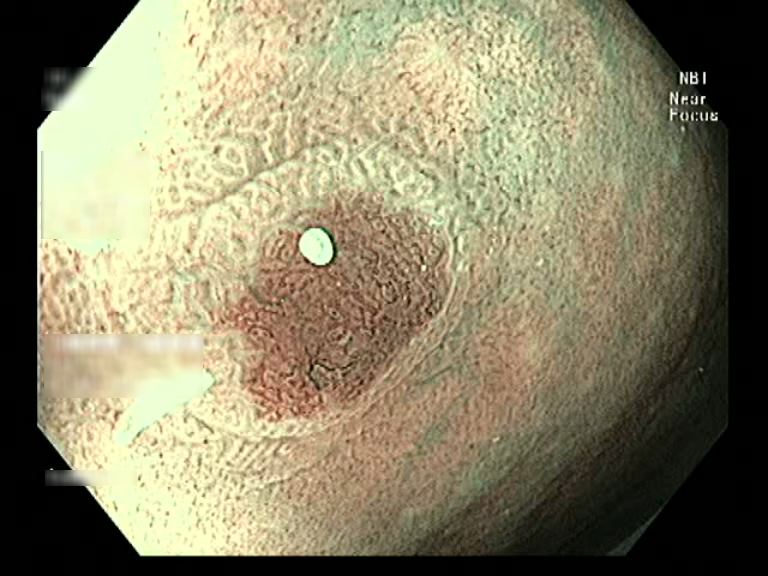

| Lesion | White Light Frame | NBI Frame | White Light Video | NBI Video | Camera Calibration |

| hyperplasic_01 |  |

|

WL.mp4 | NBI.mp4 | cam.xml |